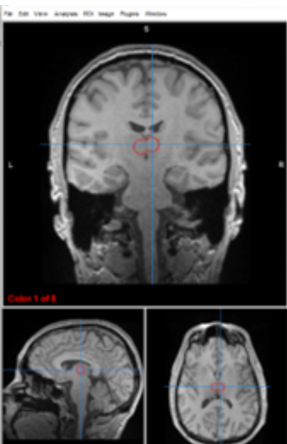

thalamus

filters information, regulates conscoiusness and sleep